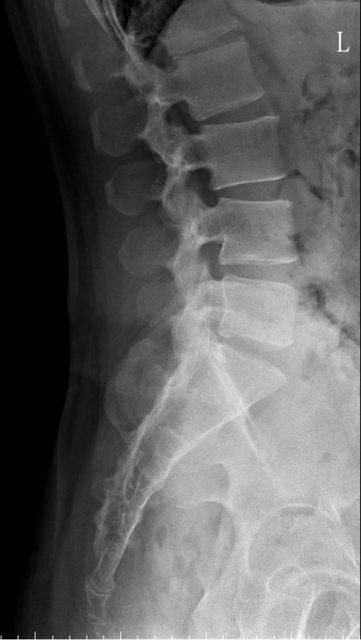

https://i.imgur.com/9HfkOHc.png

骨盆 https://i.imgur.com/h7KknkX.png

股骨頭放大特寫...左邊是右股骨 你覺得哪邊比較正常? https://i.imgur.com/16erxqZ.png

https://i.imgur.com/7NtJDKg.png

https://i.imgur.com/R4JFreK.jpg

醫生似乎很急 就問了二個問題就叫我去照X光 可能就一分鐘吧 回來看了下X光就說可能有神經壓迫 又是14天的消炎止痛藥 說還會痛再來回診或去看脊柱專科或復健科 感覺就是浪費了一天的時間排隊再排隊 沒得到答案 也沒有得到解決... 然後拿了吃越多可能洗腎越快的止痛藥 會不會下次脊柱專科也開14天消炎止痛說如果還有問題叫你去掛神經科? 為何不給我照MRI呢?我第一次去看問了MRI就還是只給我照X光 1.2期X光照了也不一定有異常,我實在不懂不用MRI的邏輯 體驗實在太差了,當然我也知道當有一百號排隊時問診就不可能細到哪怕只有15分 我想不等直接掛看看禮拜三神經科會怎解釋了 ※ 編輯: capybaradash (118.166.44.25 臺灣), 07/31/2023 14:29:17 ※ 編輯: capybaradash (118.166.44.25 臺灣), 07/31/2023 14:37:27

g17321732: 1.骨頭看起來沒大問題,x光不是放大找不一樣這麼簡單 07/31 18:18

g17321732: 3.MRI對你的幫助不大,X光已經足夠清楚,不用花冤枉錢 07/31 18:18